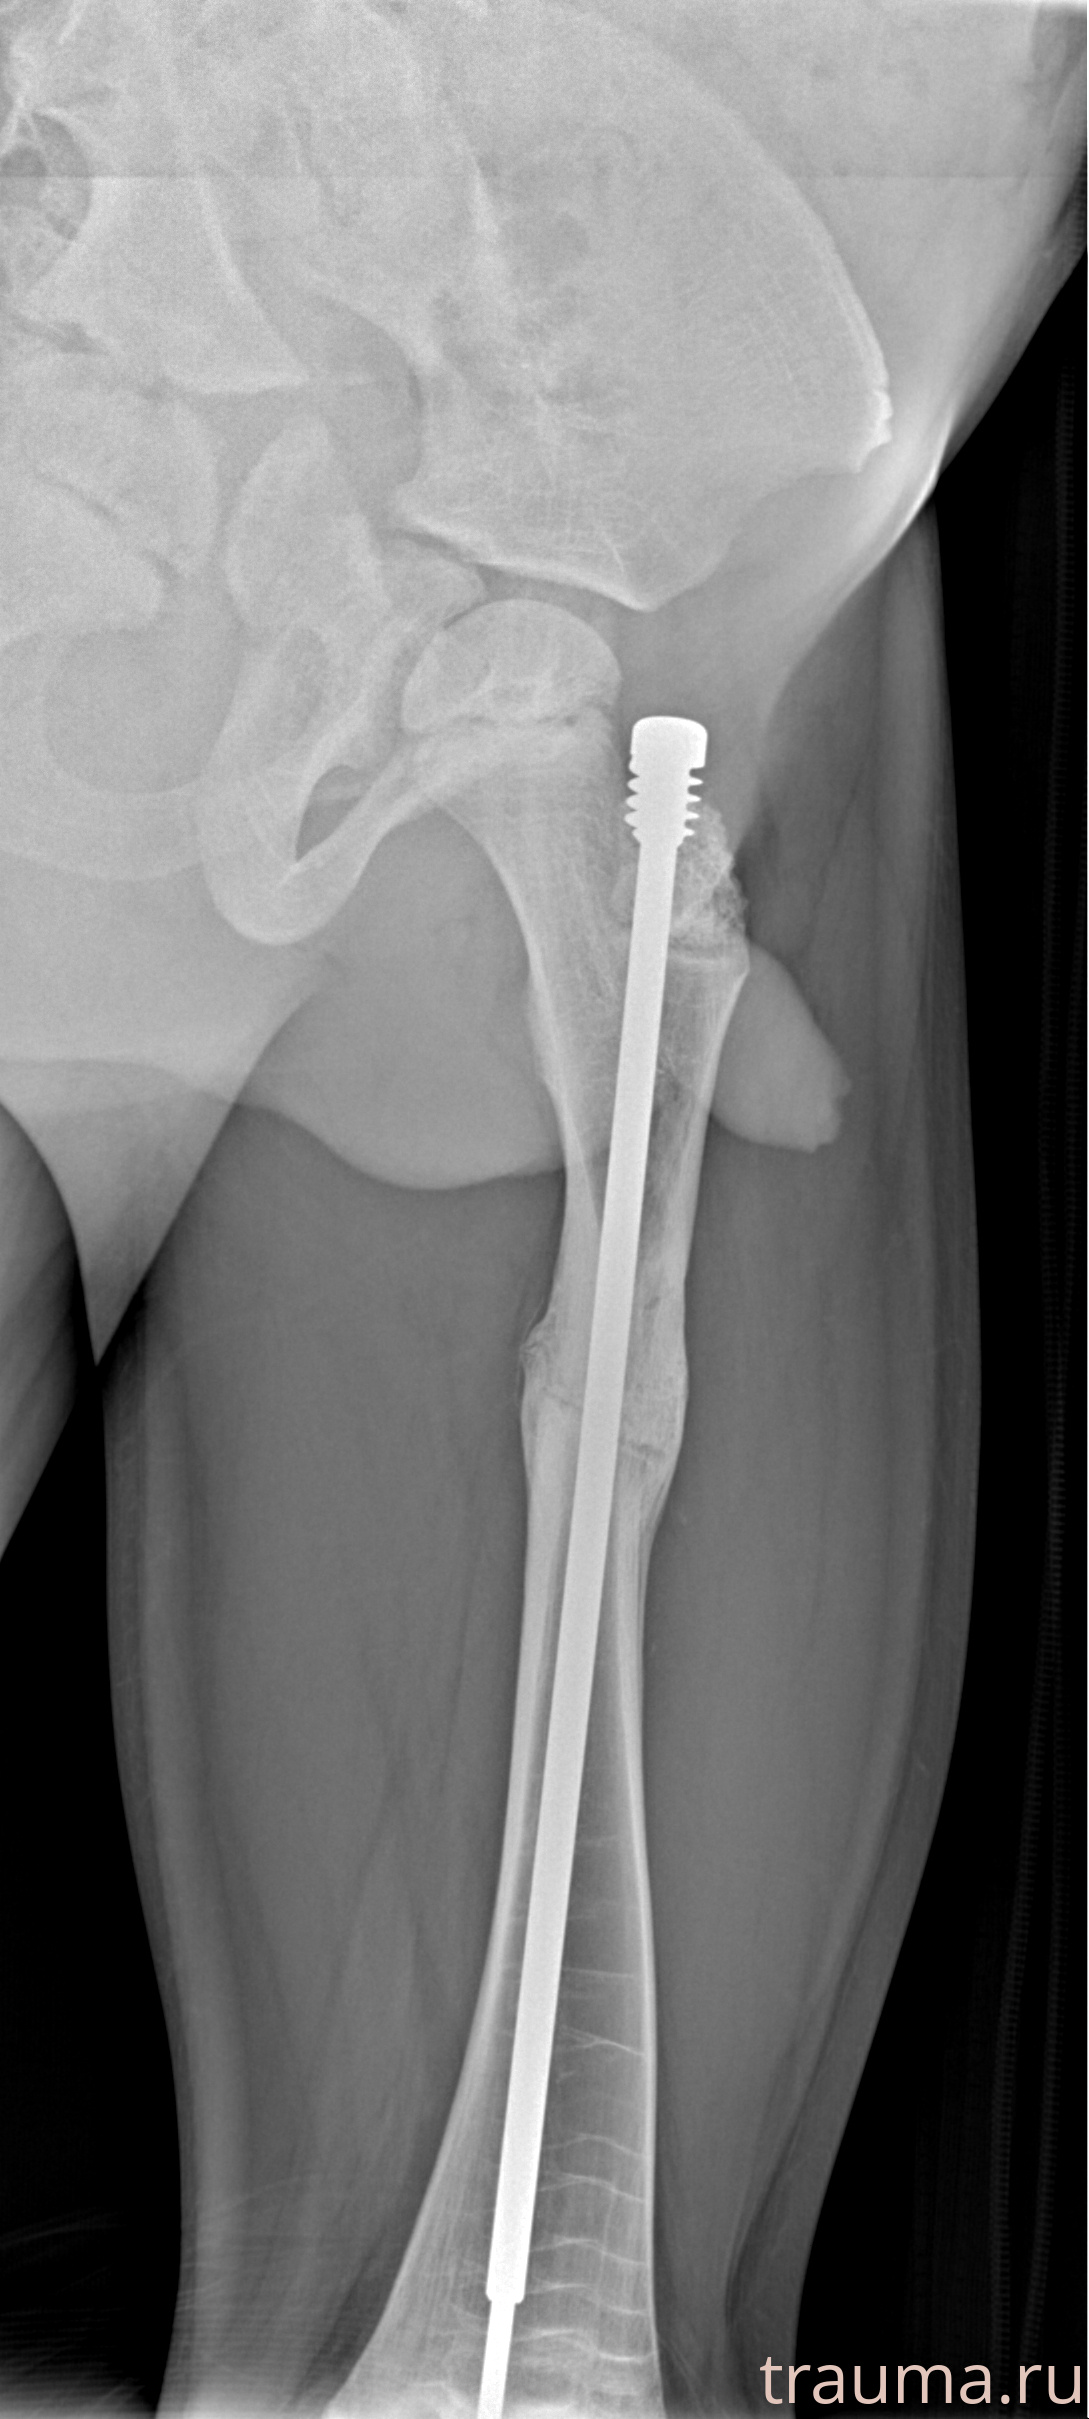

Рентгенограммы

Рентген на дому: по вашему адресу приезжает врач-рентгенолог, травматолог-ортопед с мобильным рентгеновским аппаратом, проводит диагностику травмы или заболевания, делает необходимые рентгенограммы, дает рекомендации по дальнейшему лечению. Получить качественные снимки в домашних условиях возможно благодаря уникальной методике, разработанной МосРентген Центром для института  Склифосовского